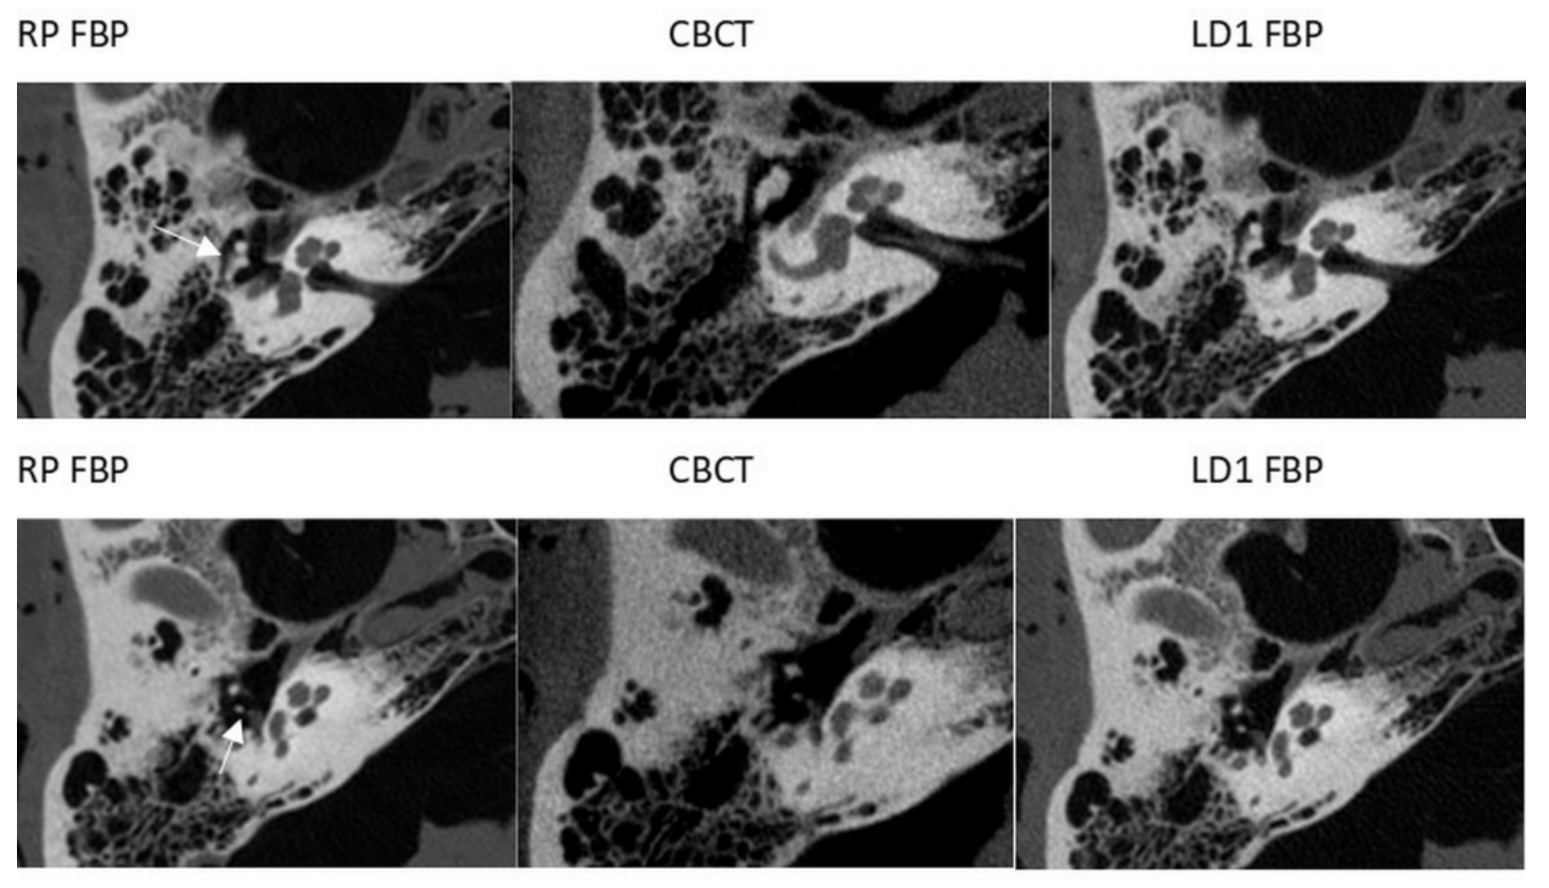

3.1. CT

3.2. CBCT

4. Discussion